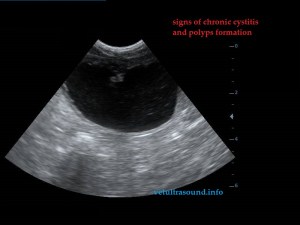

There were polyps in the urinary bladder wall and signs of cystitis.(pic4)

pic4